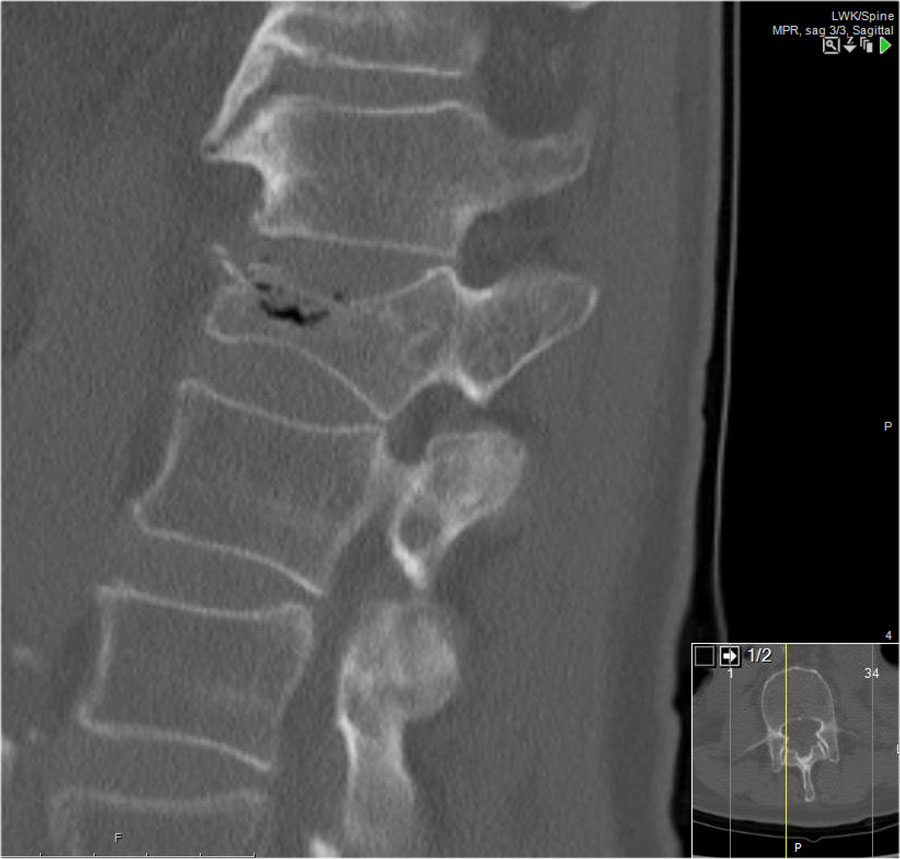

Các hình ảnh là của một bệnh nhân với hình ảnh cột sống tre điển hình do viêm cột sống dính khớp.

Sau khi ngã ngửa, không thấy gãy xương trên phim X-quang.

Tuy nhiên, CT cho thấy một đường gãy mảnh qua mặt trước thân đốt sống và cả qua mỏm gai.

Tiếp tục xem các hình ảnh MRI.